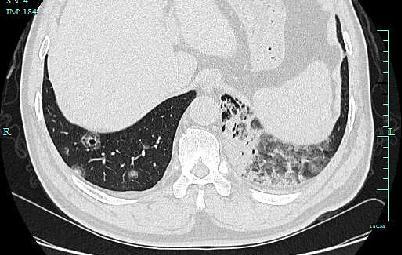

遗憾的是 , 由于张伯双肺内多发病灶 , 已经无法用手术切除 。 呼吸内科专家团队为他制定了化疗方案 , 目前张伯已接受化疗治疗 , 通过CT复查显示病灶明显缩小 , 咳血症状也明显好转 。

经过化疗后 , 张伯病灶明显缩小